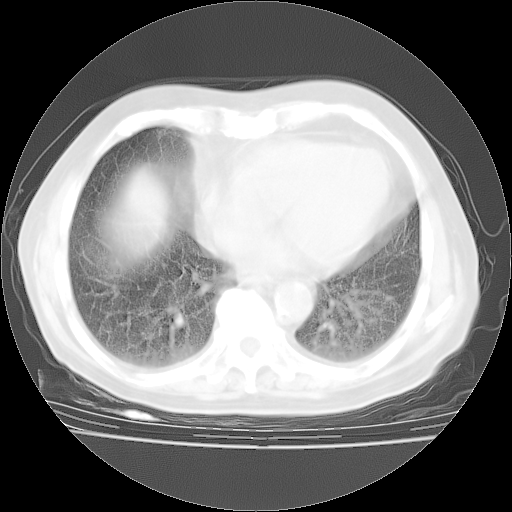

4月28日肺部CT——再次出现类似去年5月9日——透光度降低,“间质性”改变。

4月28日肺部CT——再次出现类似去年5月9日——磨玻璃样、间有“粟粒样”改变。

4月28日肺部CT